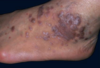

erythema multiforme

acute eruption

HSV, mycoplasma

young adults

target lesions

self limited